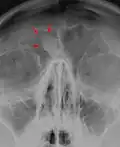

Osteoma of the frontal sinus seen on x-ray -